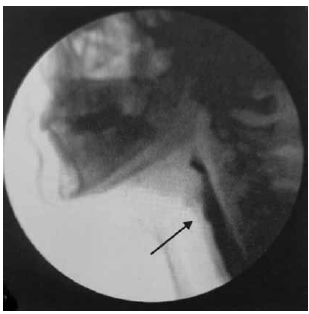

Segundo Magalhães e Magnoni (2022), nos pacientes oncológicos, principalmente com câncer de cabeça e pescoço, há modificações na anatomia e é importante conhecê-las para melhor avaliação.

Observe o exame a seguir:

(Magalhães e Magnoni: Disfagia orofaríngea no adulto em ambiente hospitalar. Rubio, 2022. p. 89)

O resultado do exame apresentado é compatível com um exemplo de